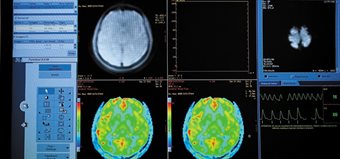

The laboratory is equipped with the latest 3 Tesla (3T) Philips Ingenia Wide Bore MRI system having an open bore diameter of 70 cm giving greater level of patient comfort.

High quality images with improved SNR are achieved with the latest digital broadband MR architecture on this scanner. This enables the lab to offer structural and functional imaging.

It is equipped with a comprehensive set of coils for abdominal, MSK and head imaging, and also has multinuclear and elastography capabilities.

This scanner is also equipped with physiological monitoring capability, and can be used with MR compatible EMG and EEG.